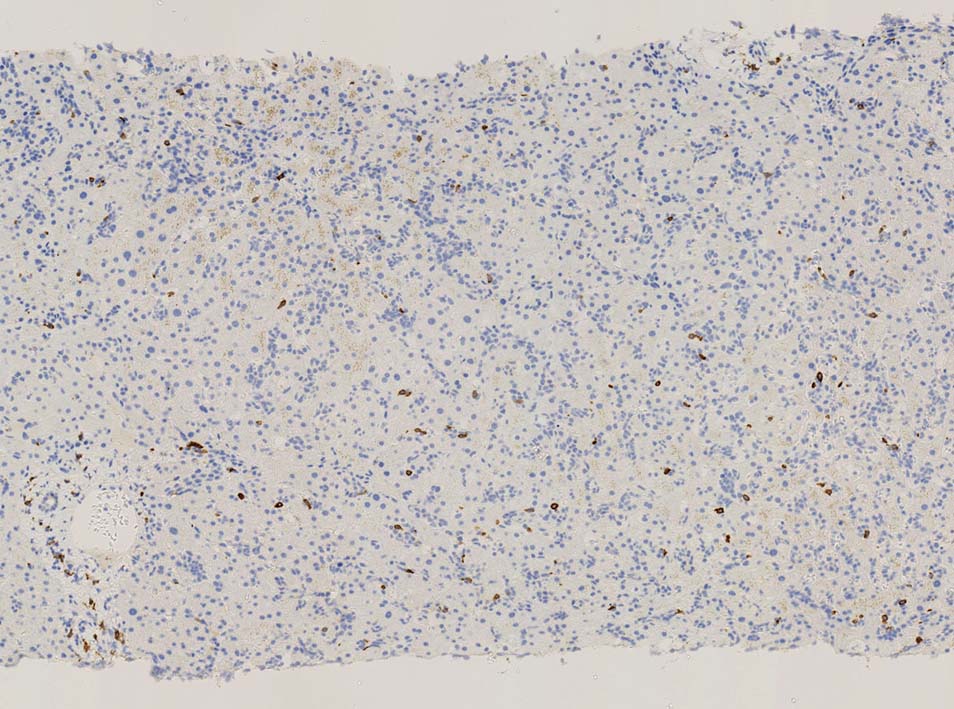

肝針生検組織; 類洞に細胞浸潤が認められ, 非浸潤部との境界がぼんやりと認められる. 類洞と異なり, グリソン鞘は腫瘍細胞の浸潤が乏しいか, ほとんど認められない.

類洞内に浸潤増殖するリンパ腫細胞: 類円形・長円, 瓜状の核をもつ,細胞質の乏しい細胞(サムネイル画像のクリックで大きな画像が見られます)

類洞内で増殖する腫瘍細胞はCD3+, CD7+のT-cellであるがCD5発現が弱く, 異常なT-cellである.

CD4は類洞内皮/macrophageの一部が陽性であるが, 類洞内腫瘍細胞の多くは陰性を示す(陽性と間違えないこと). CD8陰性. CD20陽性リンパ球はごく少ない.

TIA1は陽性であるが, granzymeBは陰性細胞が多い.